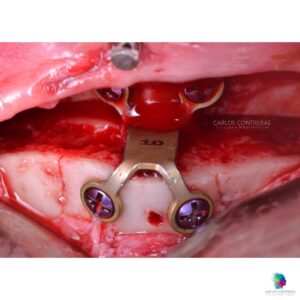

La mentoplastía, también conocida como cirugía del mentón, es un procedimiento estético y funcional diseñado para mejorar las proporciones faciales. Este tratamiento se basa en la remodelación del hueso para alcanzar una apariencia más equilibrada y armoniosa, y en algunos pacientes como parte del tratamiento para apnea del sueño o ronquidos. En algunos casos cuando el objetivo sea netamente estético, es factible incluir la colocación de un implante de silicona.

- La Cirugía: La mentoplastía se realiza generalmente bajo anestesia local con sedación o anestesia general, según la complejidad del caso. El procedimiento puede durar entre una y dos horas.

- Reducción del Mentón: Involucra la eliminación o reestructuración del hueso para reducir el tamaño del mentón prominente.

- Implante de Mentón: De ser necesario, se inserta un implante de silicona a través de una pequeña incisión dentro de la boca o bajo el mentón.